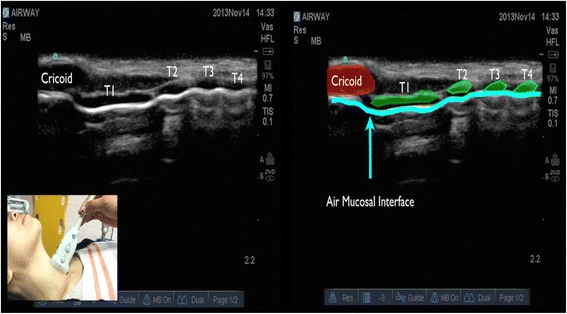

Nel piano longitudinale, l’aspetto ipoecogeno della cartilagine cricoide è visto come una ” gobba ” (Fig.1 ) e nel piano trasversale come una struttura ovale ipoecogena (Fig.2 ).

La cartilagine tracheale nel piano longitudinale è vista come un “filo di perline” (Fig.3 ) e una U rovesciata nel piano trasversale (Fig.4 ). Una linea iperecogena lineare vista posteriormente sul piano trasversale e longitudinale della trachea è formata da artefatti da riverbero dall’interfaccia aria-mucosa.